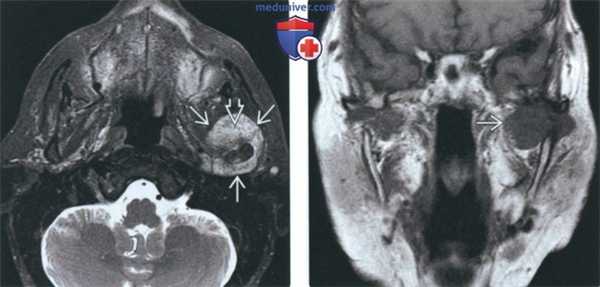

(Слева) На сагиттальной МРТ (Т1 ВИ) у этого же пациента вокруг мыщелка визуализируется многокамерное объемное образование, вовлекающее суставную ямку и большое крыло клиновидной коои.

(Справа) На аксиальной MPT (Т1 ВИ С+ FS) у этого же пациента определяется обширное контрааное усиление солидного объемного образования, окружающего мыщелок, что позволяет исключить его воспалительный характер.

(Слева) На аксиальной МРТ (Т2ВИ FS) у пациента с ХС левого ВНЧС определяется мягкотканный компонент с неоднородным, но в целом высокоинтенсивным Т2 сигналом, типичным для хондроидных опухолей. Точечные гипоинтенсивные очаги отражают внутриопухолевые кальцинаты.

(Справа) На корональной МРТ (Т1ВИС+ FS) у этого же пациента определяется интенсивное накопление контраста в объемном образовании сустава, что подтверждает его солидную структуру и позволяет исключить жидкость в суставе, растягивающую капсулу.